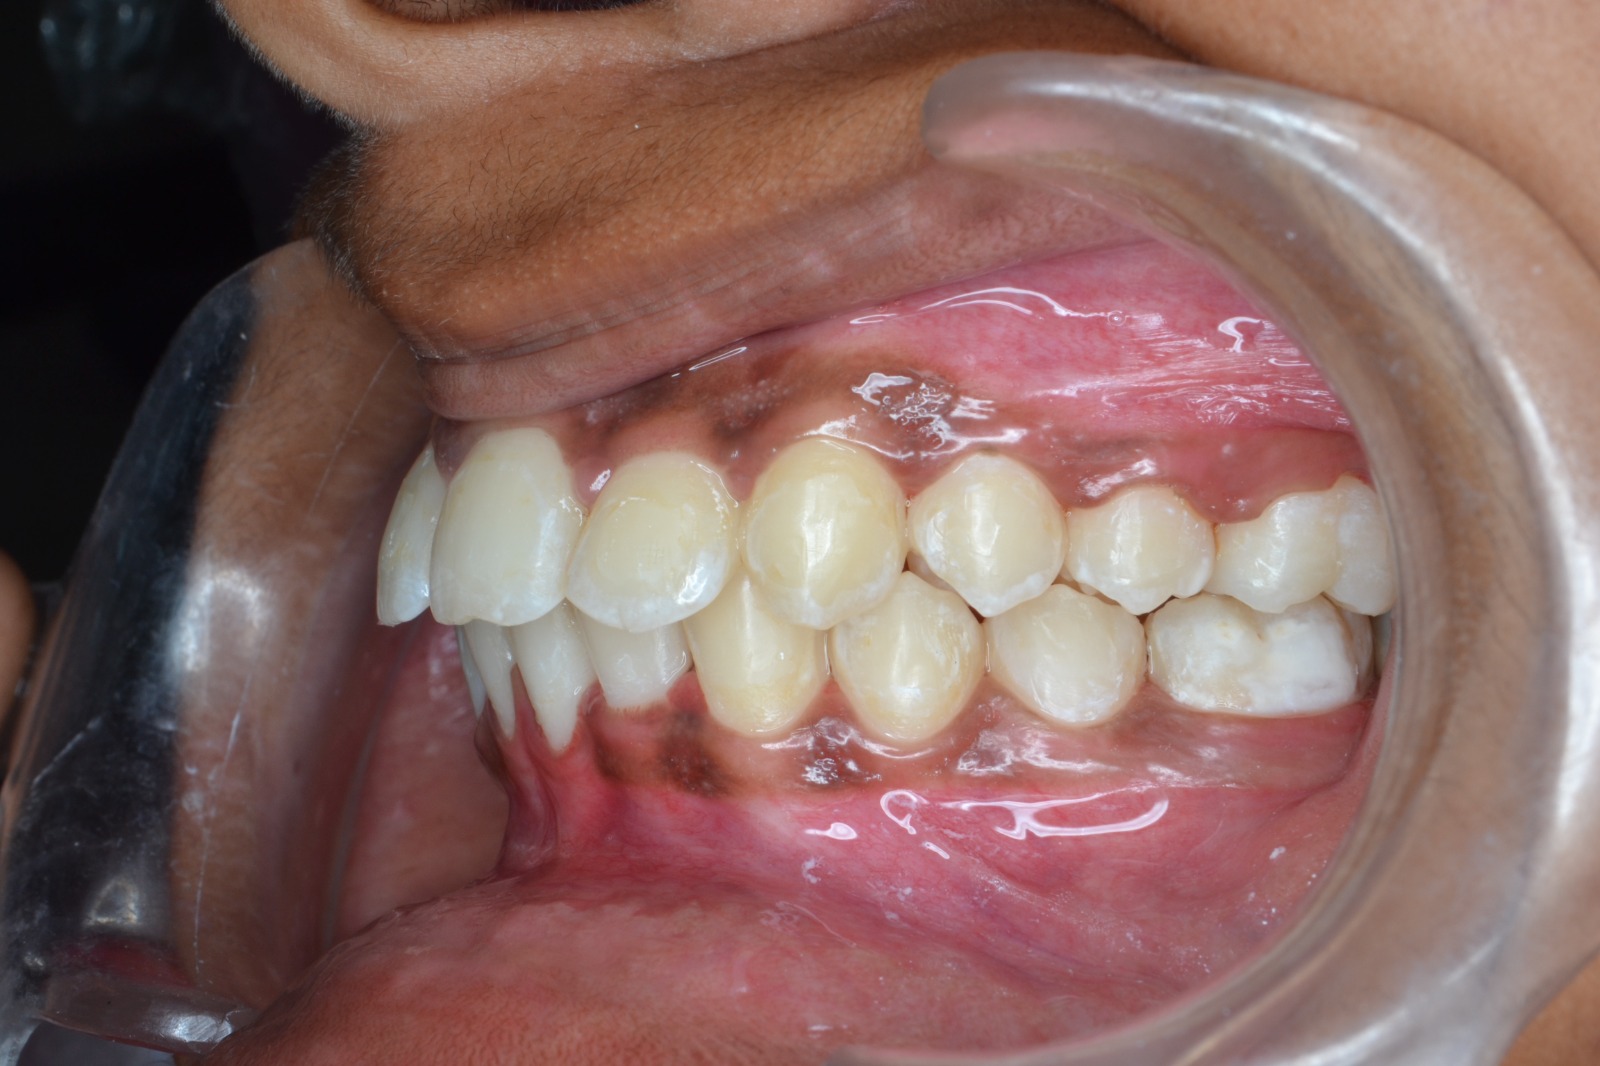

Sairam dental care located in Dharmapuri, with Leading Dentist In Oddapatti, is the Dental Hospital with exclusive root canal, Braces & Invisalign center. Led by renowned Drs Raghuraaman ( Periodontist) and Nivetha Raghuraaman ( Orthodontist) Sairam dental care offers gum treatment with expertise in laser, root canal treatment and digital smile correction with advanced technology aim to focus on aesthetics, comfort and precision. The clinic also specializes in Invisalign treatment, digital smile makeover, laser gum care, dental implants, root canal therapy, extractions and full-mouth rehabilitation blending compassionate care and clinical excellence.

Our professional, experienced, and passionate dentists make us the best choice for Invisalign treatment in Dharmapuri, providing top-notch dental services.